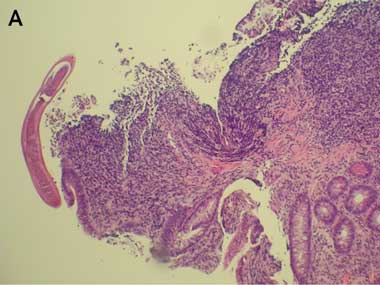

A bone marrow biopsy showed a marked eosinophilia (40%–60%), but was normocellular with a normal karyotype on cytogenetic analysis. Endoscopy showed small duodenal erosions. Biopsies of the duodenum, ileum and colon showed an inflammatory cell infiltrate, including plentiful eosinophils (Box 2). Repeated stool specimens yielded only Blastocystis hominis cysts, not considered relevant to the clinical setting. A terminal urine specimen revealed no schistosome eggs, and serological tests for Strongyloides, Fasciola and Schistosoma were negative.

2 Sample from Patient 2

Duodenal biopsy showing a profuse eosinophilic infiltrate.